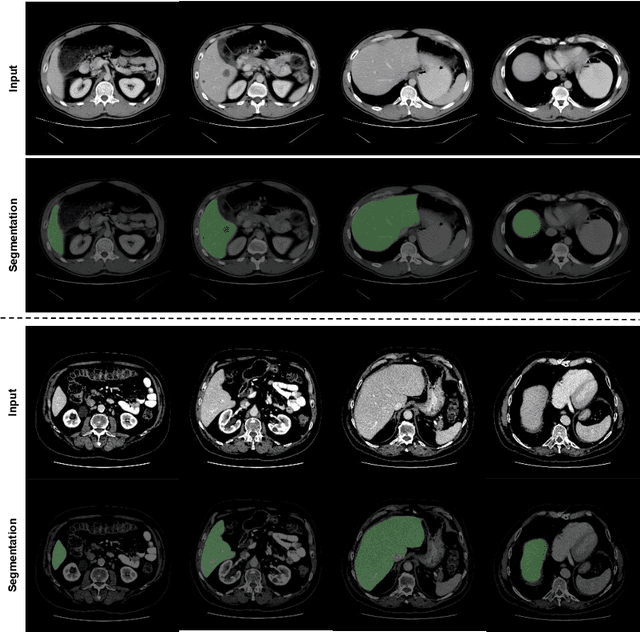

Abstract:Automated liver segmentation from radiology scans (CT, MRI) can improve surgery and therapy planning and follow-up assessment in addition to conventional use for diagnosis and prognosis. Although convolutional neural networks (CNNs) have become the standard image segmentation tasks, more recently this has started to change towards Transformers based architectures because Transformers are taking advantage of capturing long range dependence modeling capability in signals, so called attention mechanism. In this study, we propose a new segmentation approach using a hybrid approach combining the Transformer(s) with the Generative Adversarial Network (GAN) approach. The premise behind this choice is that the self-attention mechanism of the Transformers allows the network to aggregate the high dimensional feature and provide global information modeling. This mechanism provides better segmentation performance compared with traditional methods. Furthermore, we encode this generator into the GAN based architecture so that the discriminator network in the GAN can classify the credibility of the generated segmentation masks compared with the real masks coming from human (expert) annotations. This allows us to extract the high dimensional topology information in the mask for biomedical image segmentation and provide more reliable segmentation results. Our model achieved a high dice coefficient of 0.9433, recall of 0.9515, and precision of 0.9376 and outperformed other Transformer based approaches.